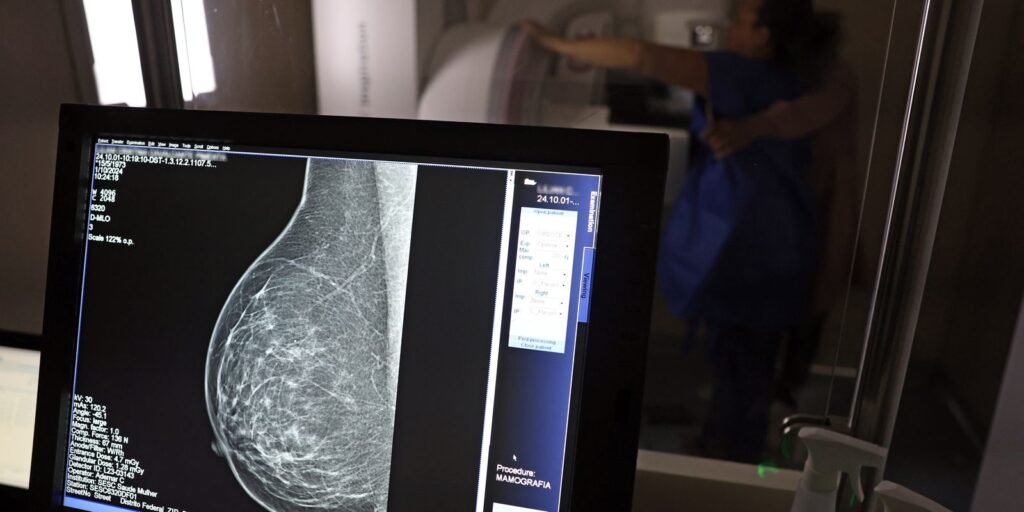

No mês de conscientização sobre o câncer de mama, um relatório destaca a importância de acesso igualitário ao rastreamento e tratamento da doença. Segundo o Atlas da Radiologia no Brasil, do Colégio Brasileiro de Radiologia e Diagnóstico por Imagem (CBR), o acesso aos mamógrafos ainda é um desafio.![]()

O país tem 6.826 equipamentos registrados, sendo 96% em funcionamento. Metade deles está disponível no Sistema Único de Saúde (SUS), responsável por atender 75% da população. Isso equivale a 2,13 mamógrafos por 100 mil habitantes dependentes do SUS.

Na saúde suplementar, que cobre 25% da população, o cenário é mais favorável: 6,54 aparelhos por 100 mil beneficiárias, quase o triplo da rede pública. O Acre exemplifica essa disparidade — são 35,38 mamógrafos por 100 mil habitantes na rede privada, contra 0,84 no SUS.

Há disparidades regionais. Roraima tem a menor proporção (1,53 por 100 mil), seguida do Ceará (2,23) e Pará (2,25). A Paraíba lidera o ranking (4,32), à frente do Distrito Federal (4,26) e do Rio de Janeiro (3,93).

O Brasil tem uma cobertura muito baixa de mamografias: 24%. O ideal recomendado pela Organização Mundial da Saúde é de 70%. Mesmo em lugares como o estado de São Paulo, que tem a maior concentração de mamógrafos do país, a taxa gira em torno de 26%.

Em setembro, o Ministério da Saúde ampliou as diretrizes de rastreamento, recomendando que mulheres entre 40 e 49 anos realizem mamografias, mesmo sem sintomas. De acordo com o Instituto Nacional do Câncer (Imca), mais de 73 mil mulheres recebem o diagnóstico de câncer de mama anualmente no Brasil.